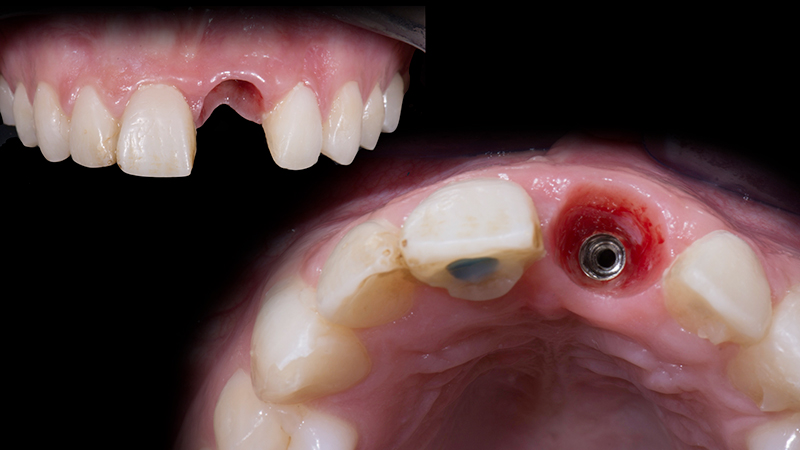

Guarigione a 3 mesi

Fig. 16d - Guarigione a 3 mesi.

Aspetto dei tessuti molli dopo la rimozione del provvisorio

Fig. 17 - Aspetto dei tessuti molli dopo la rimozione del provvisorio.